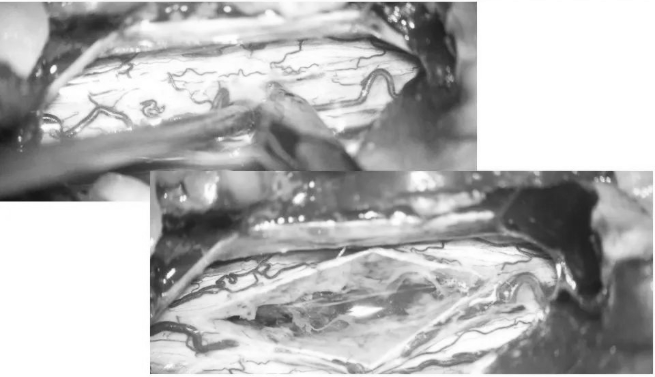

▼沿后正中切开,即可见含铁血黄素沉积带及陈旧性血凝块

▼用细致的双较或者剥离子沿含铁血黄素沉积带,分离海绵状血管瘤并电凝切断供血分支血管

▼逐步显露血管瘤腹侧面